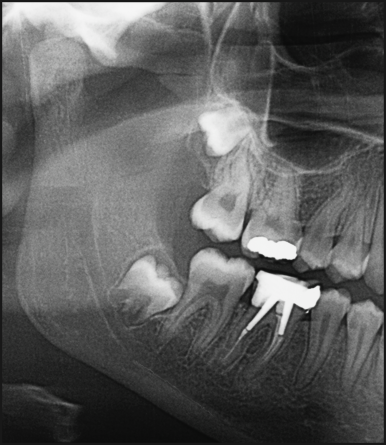

사랑니 발치는 잇몸을 절개하고

치아를 쪼개서 꺼내는..

사실상 구강 내에서 이루어지는 작은 수술입니다.